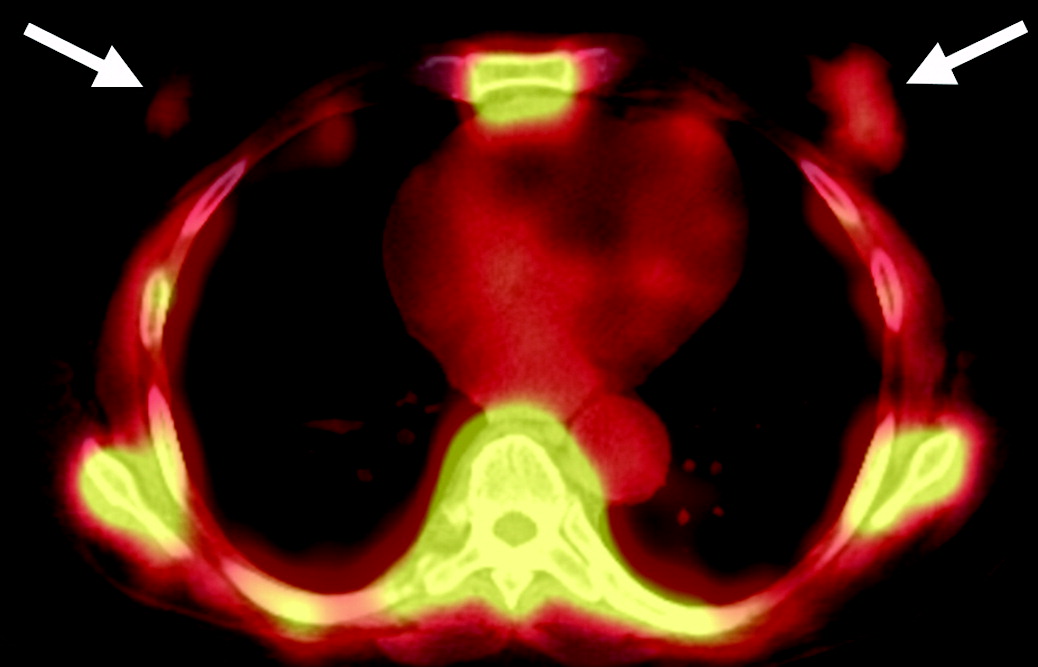

Metastasi costali e pleuriche con versamento pleurico in una donna di 63 anni con tumore al seno.

La scintigrafia ossea con 99mTc-MDP evidenzia una lieve ipercaptazione diffusa che ricalca l’emitorace destro, causata verosimilmente dall’accumulo di tracciante nel liquido pleurico maligno. È inoltre visibile una captazione longitudinale a carico dell’arco posteriore dell’XI costa destra. La TC conferma la natura della captazione, evidenziando il versamento pleurico, un ispessimento pleurico e le iniziali alterazioni osteosclerotiche a carico della costa interessata. Il caso dimostra come la scintigrafia ossea possa rilevare non solo le localizzazioni secondarie scheletriche dirette, ma anche segni indiretti di patologia extra-ossea adiacente (come la captazione pleurica).